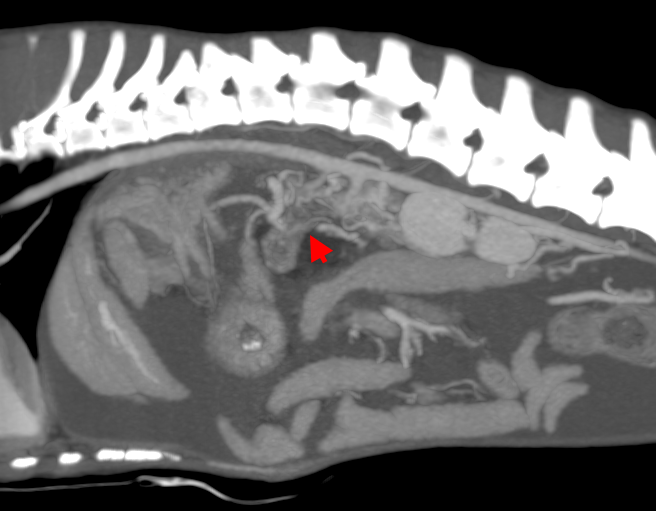

АВМ печени принято делить на правосторонние и левосторонние. Последние подразделяются на левую латеральную и медиальную мальформации в зависимости от положения выносящей вены (рис. 2).

Диагностика печеночных АВМ осуществляется с применением КТ-ангиографии, выявляющей сосудистую сеть (или «гнездо»), образованную ветвями приносящей печеночной, гастродуоденальной, левой желудочной и другими артериями, через которую происходит слияние с воротной веной (рис. 3). Артериальная фаза является самой важной в идентификации приносящих ветвей артериовенозной мальформации. АВМ имеют тенденцию изменяться со временем, в связи с этим КТ-ангиографию рекомендуют проводить как можно ближе к дате планируемого хирургического вмешательства.